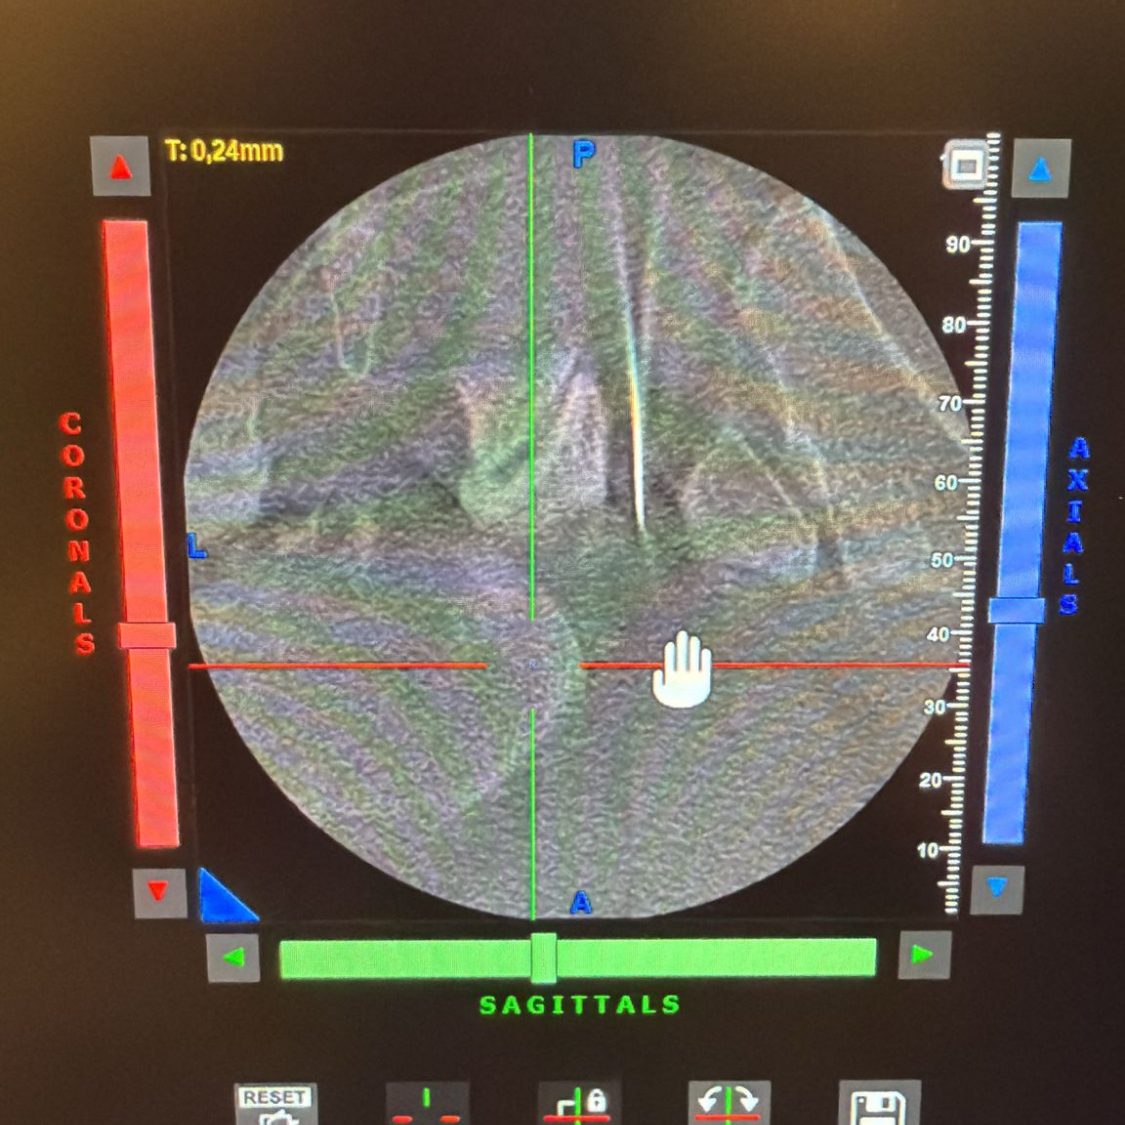

Präzise und schonende PRT-Behandlungen für gezielte Schmerzreduktion ohne großen Eingriff unter Sicht in "der Röhre" (DVT/CT)

Modernste Techniken ermöglichen eine genaue Analyse Ihrer Rückenbeschwerden für passgenaue Therapie. Zusätzlich zu den bekannten bildgebenden Verfahren steht Ihnen bei uns ein DVT-Gerät/CT der neuesten Generation zur Verfügung.